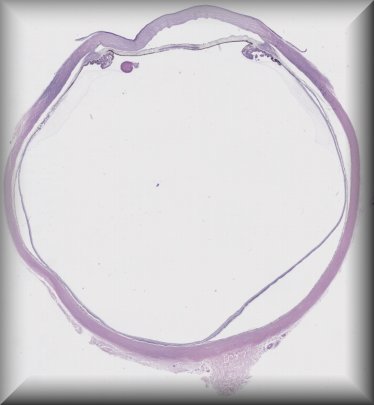

Tatyana Milman (Philadelphia): 49-year-old female underwent penetrating keratoplasty for slowly progressive glare and "brown cornea". |

![]() |